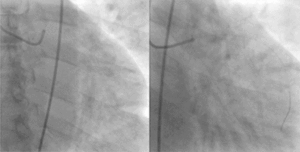

![]() A coronary angiogram (an X-ray with radio-opaque contrast in the coronary arteries) that shows the left coronary circulation. The distal left main coronary artery (LMCA) is in the left upper quadrant of the image. Its main branches (also visible) are the left circumflex artery (LCX), which courses top-to-bottom initially and then toward the centre/bottom, and the left anterior descending (LAD) artery, which courses from left-to-right on the image and then courses down the middle of the image to project underneath of the distal LCX. The LAD, as is usual, has two large diagonal branches, which arise at the centre-top of the image and course toward the centre/right of the image. | |